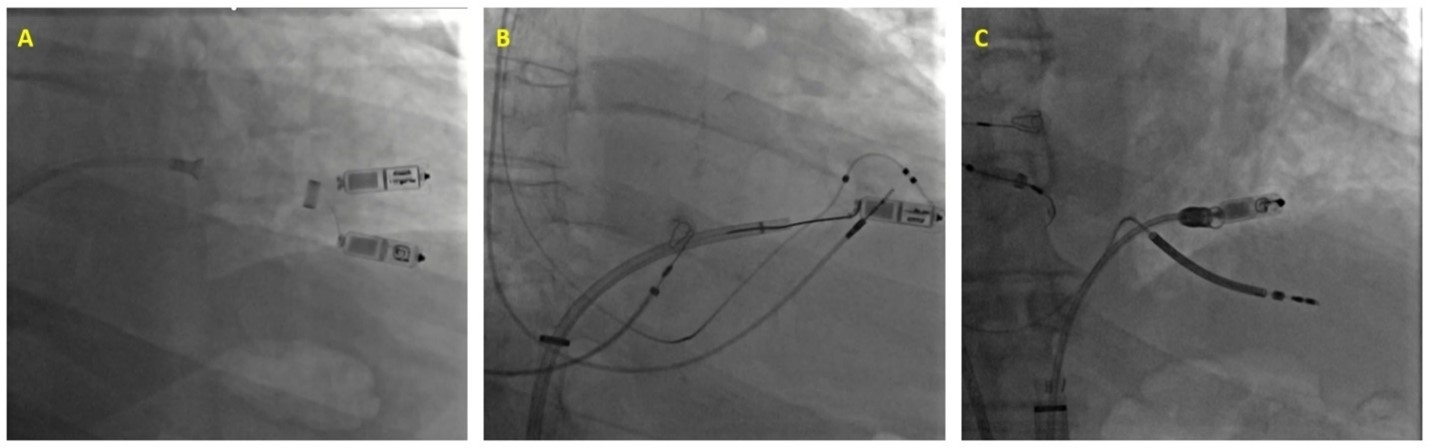

Case 1: A 72 year old male with atrial fibrillation (AF) and tachy-brady syndrome underwent Micra implantation. On post-procedure day 2, pacing thresholds were unacceptably elevated. A new Micra device was deployed; subsequently, a microsnare was placed through the Micra delivery catheter and the docking button of the old Micra was successfully snared (Figure A). The old Micra was then captured over the delivery catheter and removed from the body.

Case 2: A 76 year old male underwent Micra implantation and AV node ablation for AF with persistent tachycardia. One month later, he presented with heart failure and interval decrease in ejection fraction from 66% to 33%. After biventricular leads were implanted, an Agilis catheter was advanced towards the Micra. The docking button was successfully snared with a gooseneck snare (Figure B), and the Micra was extracted with gentle traction.

Case 3: A 76 year old male with complete heart block and longstanding persistent AF received a Micra. Nine months later, he presented with heart failure and interval decrease in ejection fraction from 55% to 25%. A defibrillator lead was implanted but no suitable CS branch was identified. The Aveir retrieval catheter was advanced and the Micra docking button was captured with the triloop snare (Figure C). The protective sleeve was advanced over the Micra and it was successfully removed. Subsequently, a left bundle area lead was placed.